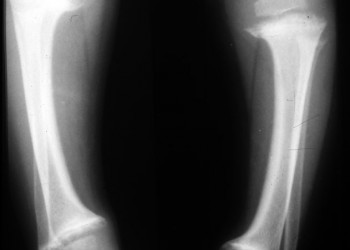

Rahitismul și osteomalacia

Osteomalacia (rahitismul la copii) reprezinta o mineralizare osoasa inadecvata cauzata de deficitul de vitamina D sau fosfor, diagnosis ce duce la fracturi si deformari ale oaselor, buy viagra dar si la retard de crestere în cazul rahitismului. Rahitismul este specific copiilor si adolescentilor, aparând înaintea închiderii cartilajelor de crestere diafizo-epifizare.

Modificarile radiografice sunt nespecifice: fracturi, pseudofracturi, deformari articulare.